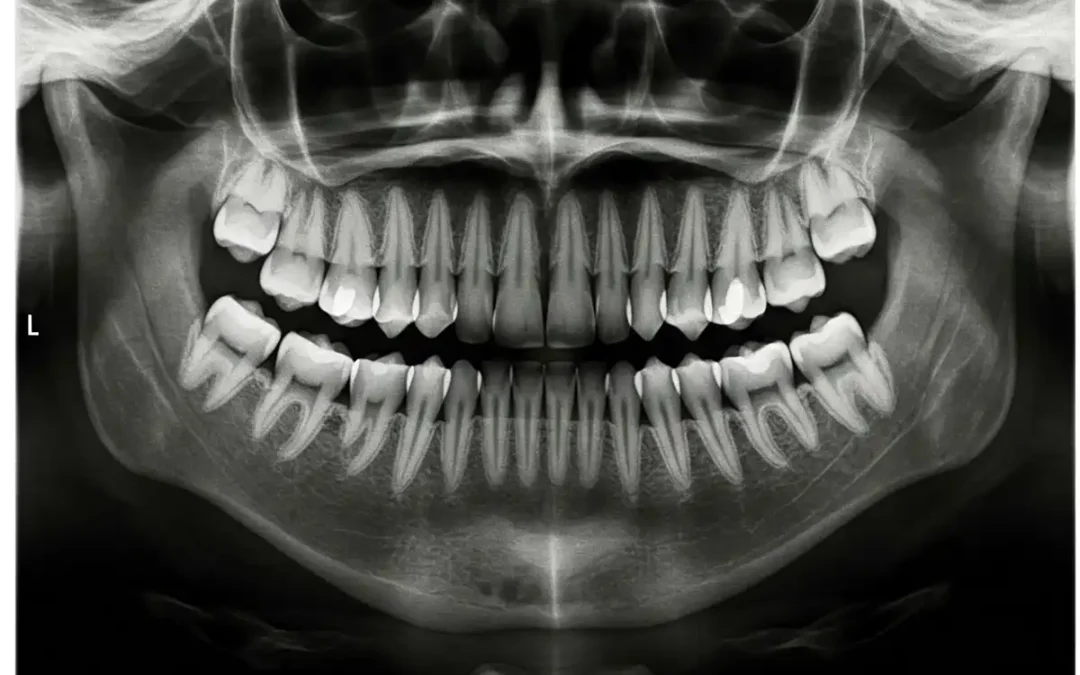

A Panorex (or panoramic) X-ray is a two-dimensional image that captures your entire mouth in one shot. This includes all your teeth, even those that haven’t erupted yet, like wisdom teeth.  It also includes.your upper and lower jaws, the temporomandibular joints (TMJ), your nasal area, and even the sinuses.

Unlike traditional intraoral X-rays where a small sensor is placed inside your mouth, the Panorex process is extraoral – the equipment moves around your head while you stand or sit comfortably.

While traditional small digital X-rays provide incredibly fine detail for individual teeth. The Panorex imaging offers a more inclusive view of your entire oral system and surrounding anatomy. Think of it like the difference between looking at a single room through a keyhole (intraoral) versus seeing the entire house from above (Panorex).

This broad perspective is crucial for identifying issues that might not be visible on smaller X-rays, providing essential context for your overall oral health.